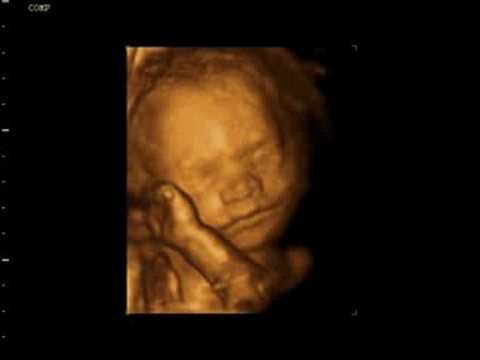

Faszinierende Ultraschallbilder

Ultraschallbilder bieten faszinierende Einblicke in

verschiedene Stadien

des Kindes im Mutterleib und veranschaulichen seine Entwicklung.

28. Woche